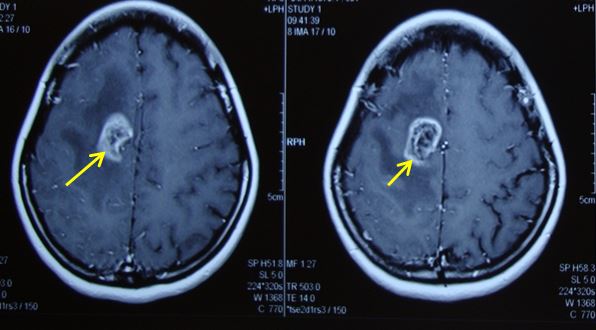

Dấu hiệu cận lâm sàng: trên hình ảnh chụp cộng hưởng từ, khối u đã nhỏ hơn so với trước điều trị, không còn ngấm thuốc, không còn phù não. Trên xung cộng hưởng từ phổ chất chuyển hóa Cholin giảm

Hình ảnh khối u trên phim chụp cộng hưởng từ sau điều trị